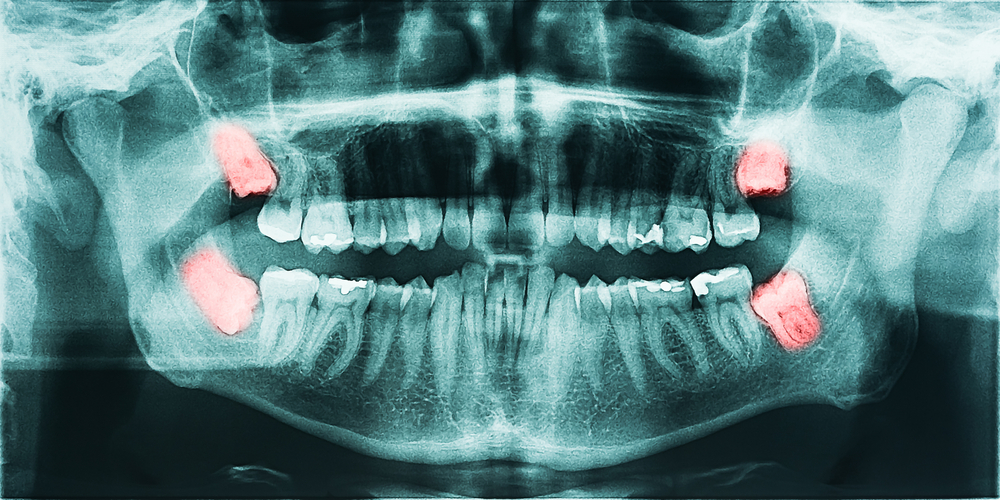

20 yaş dişleri (3. Büyük azılar) ağzımızda en geride yer alan dişlerdir ve genellikle anormal açılarda ve pozisyonlarda bulunurlar dolayısıyla normal fırçalamayla bakımları çok sıklıkla yetersiz kalmaktadır. Bu nedenle bu dişlerde geniş çürükler oluşmakta ya da çevresindeki dokularda enfeksiyonlar oluşabilmektedir ve bu durumda pek çok kişide cerrahi olarak çekilmeleri gerekli olur. Bu dişlerin çekimi, dişlerin pozisyonu ve gömüklük derecesine göre(tam/yarım) farklılık göstermektedir. Tamamen ağza sürmüş durumda olduklarında dikişsiz olarak çekilebildikleri gibi ağızda kısmen gözükmekteyse ya da hiç gözükmüyorsa cerrahi olarak çekilmesi ve ardından dikiş atılması gerekebilmektedir. Bu dişlerin çekimi normal diş çekiminden farklıdır ve daha fazla bilgi, tecrübe ve beceri gerektirir dolayısıyla her zaman ağız, diş ve çene cerrahisi uzmanları tarafından yapılmalıdır. Böylece işlem sonrası yaşanabilecek; komşu dişlerin kaybı ya da hasarı, ağrı, yanakta şişlik ve kanama gibi komplikasyonların şiddeti çok daha düşük ve ilaçlarla kontrol edilebilir olacaktır.Yeri gelmişken hatırlatalım, Uzman çene cerrahları, 5 yıllık diş hekimliği eğitiminin üzerine minimum 4 sene daha cerrahi eğitimi görmektedirler.

20 yaş dişleri bazı ender durumlarda ağza doğru açıda ve pozisyonda tamamen sürebilmişse ve ağız hijyeni çok doğru ve düzgün bir şekilde uygulanmaktaysa, sağlığını koruduğu sürece çekilmesinin gerekli olmadığı durumlar da olabilir. Her 20 yaş dişinin çekimi gerekli değildir.